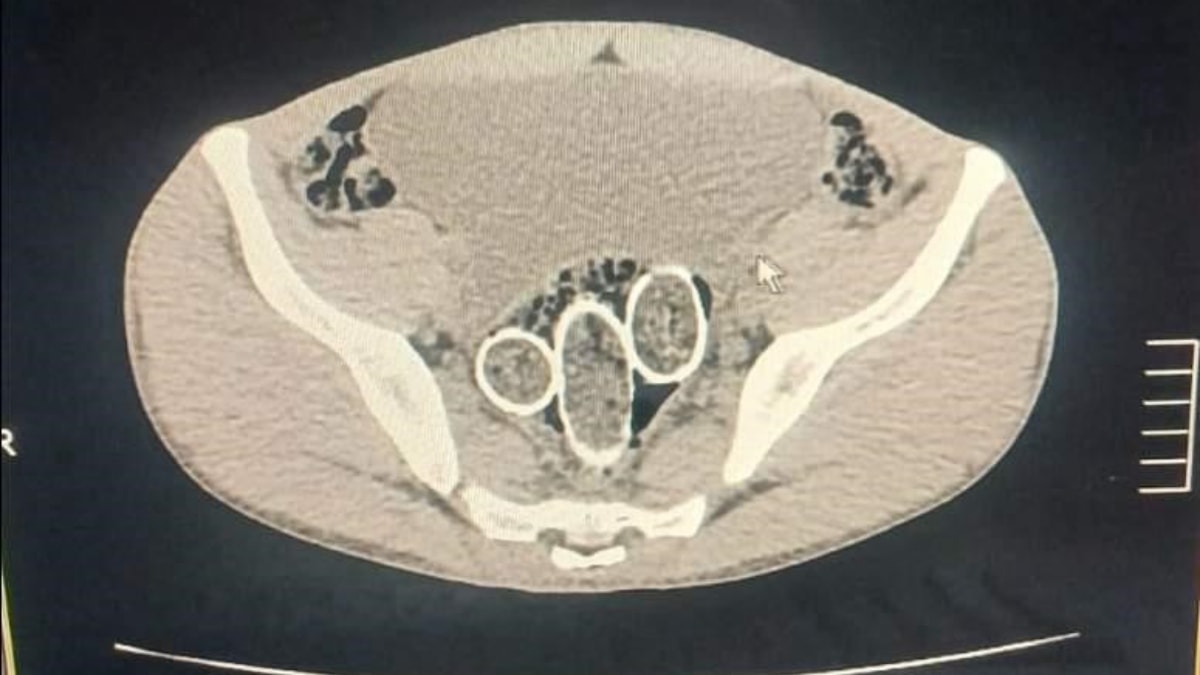

RAHİM VE MİDELERİNE UYUŞTURUCU GİZLEDİLER

Gözaltına alınan iki şahsın iç beden muayenesinde ve kullandıkları iki araçta yapılan incelemelerde, rahimde ve midede uyuşturucu madde tespit edildi.